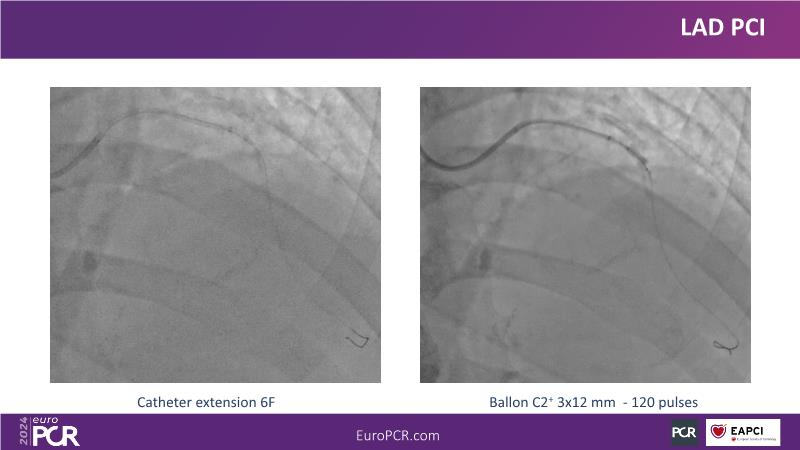

Explore this session to uncover the common association between calcium and acute coronary syndrome, and how intravascular lithotripsy (IVL) offers a safe solution for calcified lesions, with comparable procedural success rates. However, note that ACS cases involving calcium may lead to higher major adverse cardiac events (MACE). Special attention is warranted for women due to their propensity for adverse outcomes. Discover how the C2 + IVL catheter enhances procedural flexibility, yet high intracoronary imaging rates did not yield differences in MACE. Additionally, learn about the potential role of IVL in treating in-stent restenosis (ISR).

- To share clinical experience to uncover practical tips and techniques for intravascular lithotripsy in complex calcified lesions